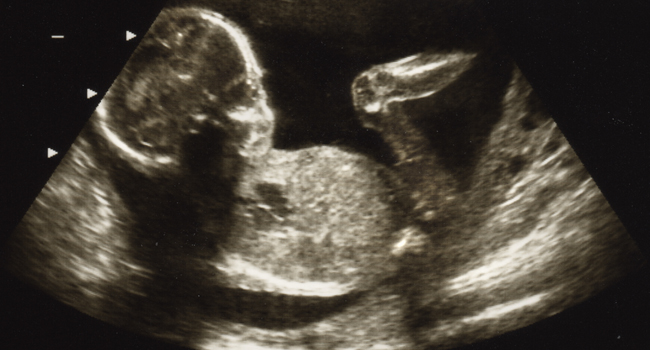

1. USG 2D

Hasil USG berupa foto hitam putih, dan hanya terlihat dari satu sisi, sehingga masih terlihat samar namun tetap dapat digunakan untuk melihat organ internal bayi. Jika dokter mencurigai ada kelainan, biasanya Anda akan disarankan melalukan USG berdimensi lebih tinggi. USG 2D dilakukan setiap trimester.